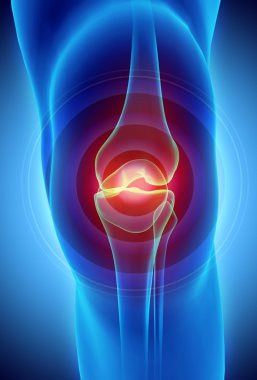

diz, anatomi, kemik

RenderkişiİnsanKadınerkekTıbbiAdamciltParmaklarKemikkolgövdebiyolojiOmuzGöğüsAcıDizkafatasıomurgaEklemKaburgaKalçaİskeletanatomiomurilikRADIUSx ışınıAğrıkadınlarKafesgörevleriçene kemiğiGöğüs kemiğiskapulaLeğen kemiğikarpalsakrumTibiaUyluk kemiğifibulaKöprücük kemiğipazı kemiğidirsek kemiğibasdiz kapağıkemiklerischiumdziewczynkiBenzer İçerikler